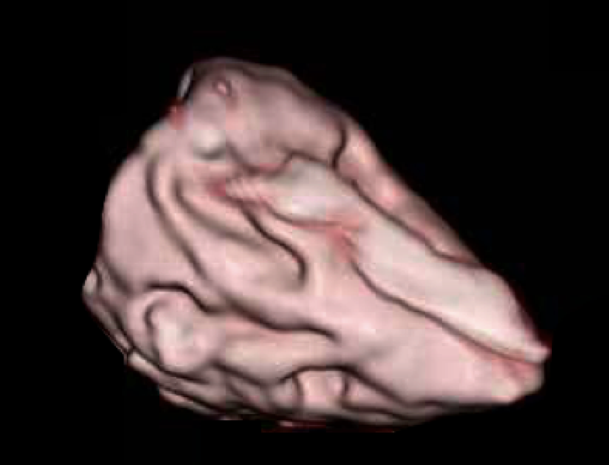

A 3D cardiac model of the single left ventricle (SLV) was specifically prepared based on the CT images of a patient who underwent Fontan surgery (Fig. 1). The patient was a 3-year-old boy with SLV, VSD, and coarctation of the aorta after undergoing the Fontan procedure. He was followed up at our hospital. We utilized digital data of a contrast CT examination that was performed at our hospital to create a 3D model of his heart. Informed consent for using the data was obtained from the patient’s parents.

Fig. 1 Cardiac model

A cardiac model of single left ventricle after Fontan procedure.